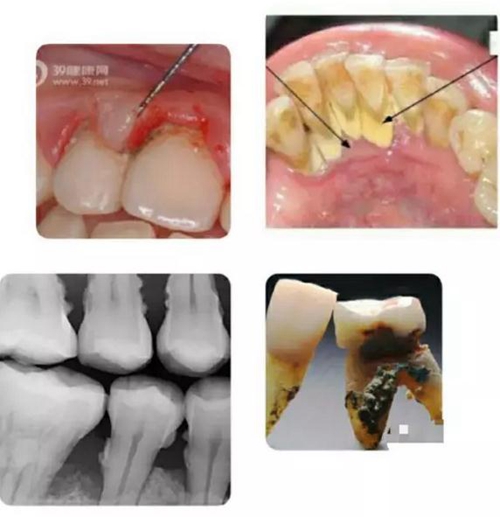

有圖有真相。上面這組圖片,自上而下從左至右,顯示了人類健康牙齒,患牙周病后,未加治療控制,以致病況越來越嚴重,最終牙齒逐漸脫落的過程。

牙周病也稱牙周炎,是包繞牙齒周圍的牙齦和牙槽骨因發(fā)生炎癥而萎縮,對牙齒逐漸失去固定支撐作用以致牙齒逐漸松脫的一類最常見牙齒疾病。

如上圖所示,無論是肉眼直視,還是在X光片上顯現(xiàn),以及拔下的牙齒之上,牙周病患者的牙根面上都可見附著著大大小小的牙結(jié)石。

寄居在牙結(jié)石里的細菌可以釋放大量毒素,導(dǎo)致牙齦發(fā)炎,溶解,與牙面分離,從而突破牙槽骨保護的第一道屏障;繼而進一步直接使牙槽骨發(fā)炎,溶解,萎縮。若無牙科治療介入,牙槽骨可以被溶解殆盡,最終牙齒自行脫落。一般來講,牙齒上的牙結(jié)石越大越多,寄居的細菌就越多,牙周病就發(fā)展得越迅速越嚴重。